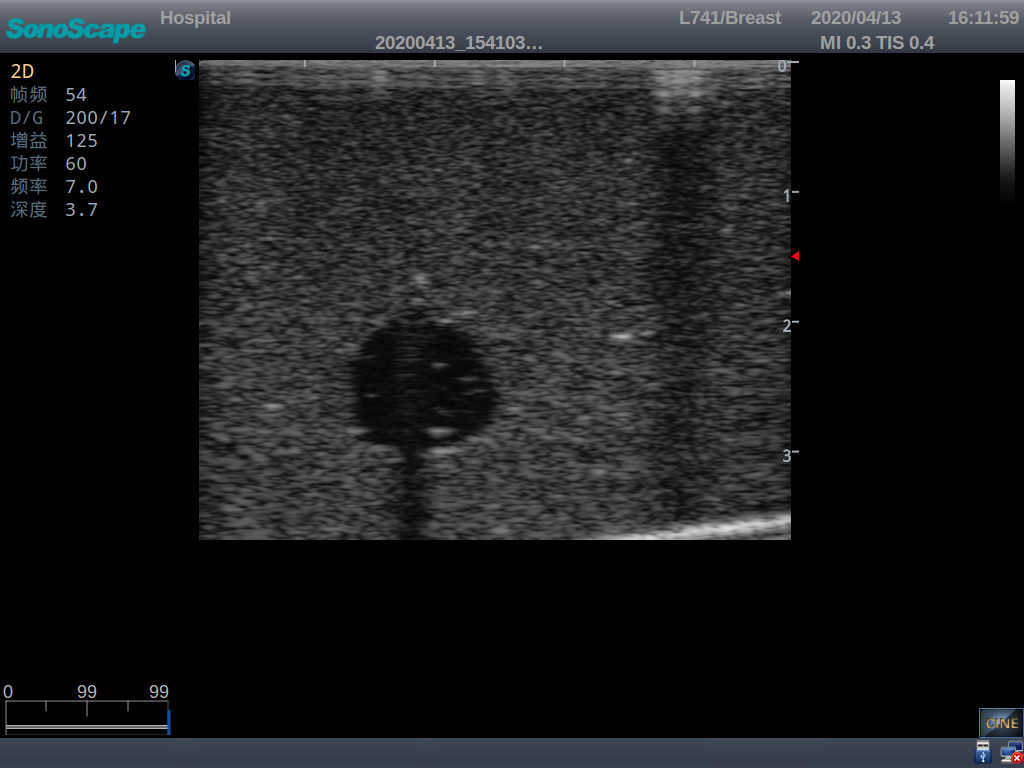

2) Each model contains 8 space-occupying lesions of varying sizes, different in touch, elasticity and ultrasonogram

4) Biomimetic material allowing users to see clear and real normal tissues and space-occupying lesions that are hyperechoic, hypoechoic and isoechoic as they would see in the clinical environment